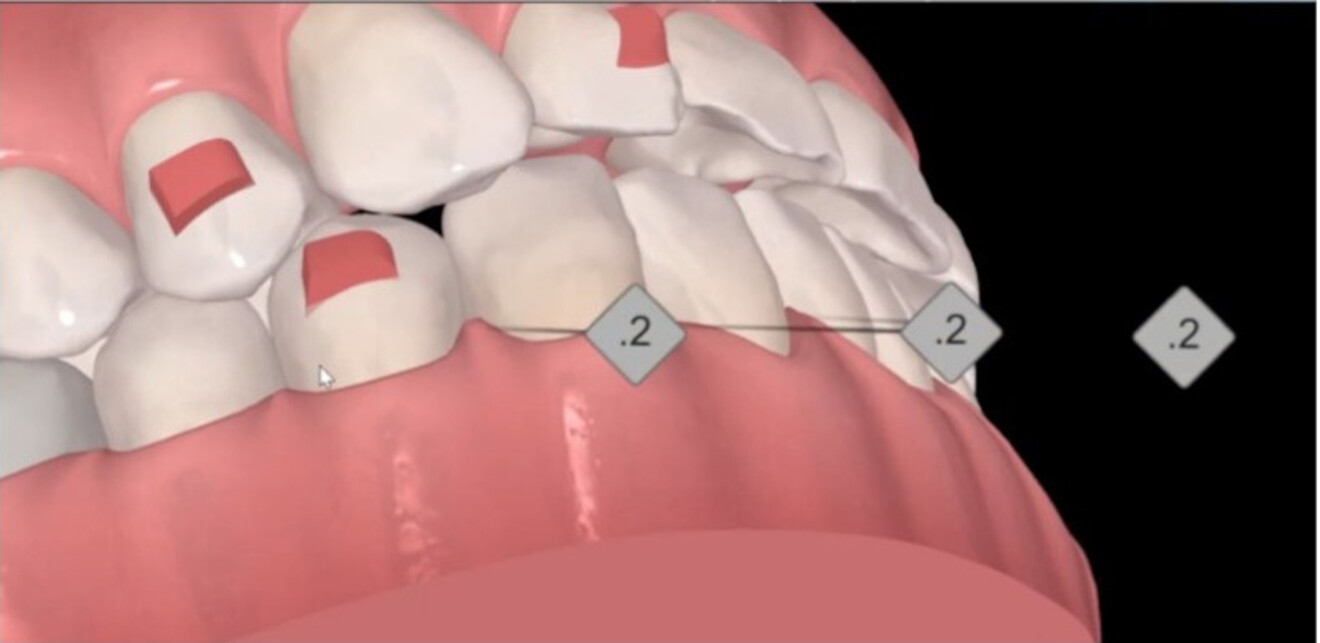

Space creation is a central factor in pre-restorative orthodontic. Treatment planning tools such as Invisalign ClinCheck (Align Technology) can simulate tooth positions, providing valuable insight into final orthodontic outcomes. Similarly, smile design or restorative overlay software allows for consideration of ideal restorative size, shape and of position. By overlaying these two digital visualisations, clinicians can better conceptualise how much space is required for the restorative phase.

The creation of space includes adjustments in the mesiodistal, vertical and buccolingual planes. Achieving space across these multiple planes, often with a combination of tooth movements, creates a more ideal pre-restorative position. For example, vertical correction helps level gingival margins and improves vertical restorative volumes, both of which are key to achieving symmetrical, additive-focused dentistry.

Figs. 1a & b: Side-by-side cross-sectional analysis of the initial (a) and post-restorative treatment position (b), highlighting vertical space creation with orthodontic treatment.